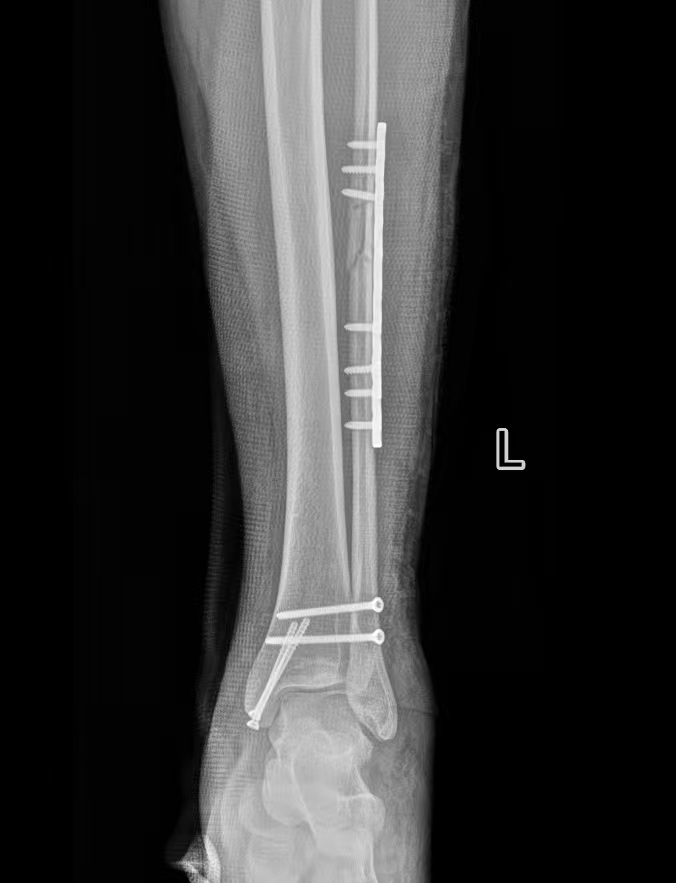

经检查确诊为旋前外旋 Ⅳ 度踝关节骨折,包含腓骨中段骨折、内踝骨折、后踝骨折及下胫腓联合分离,属于临床中结构复杂、稳定性破坏较严重的踝关节损伤。

术中严格遵循骨科诊疗规范,完成骨折复位与固定,手术过程顺利。